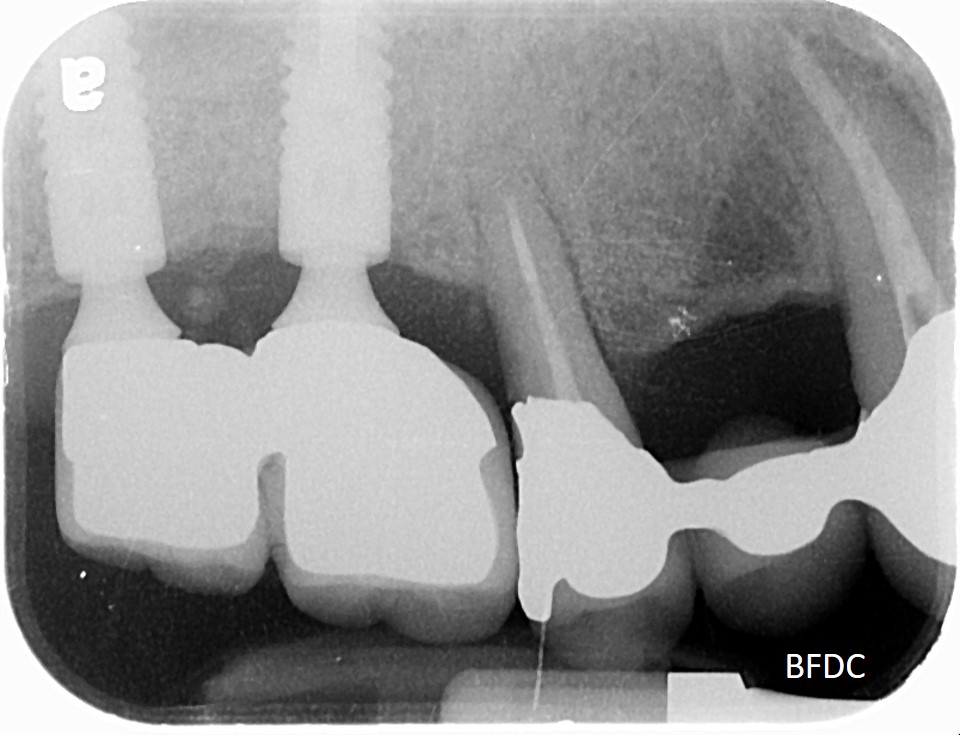

5年前,植牙剛完成,術後X光,骨癒合良好

5年後追蹤,植體周圍骨破壞